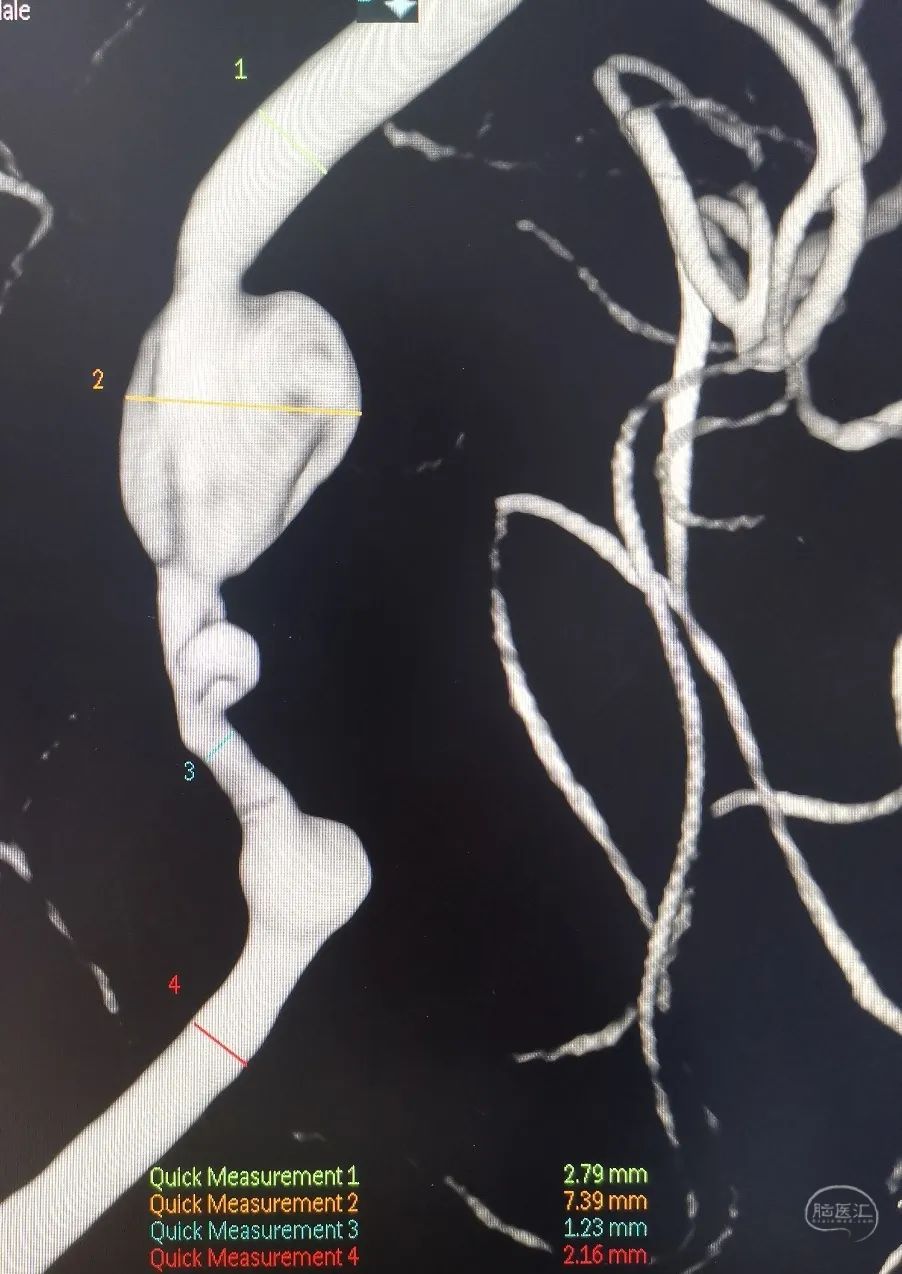

3D重建显示基底动脉下部、双椎结合部、左椎多发夹层动脉瘤:

双抗5天后行左侧椎动脉多发夹层动脉瘤Pipeline™ Flex 血流导向密网支架植入术。

将Phenom™ 27微导管超选进入左侧大脑后动脉内,释放一枚3.25×35mm Pipeline™ Flex血流导向密网支架,远端定位在动脉瘤以远7mm,在动脉瘤处推密,近端定位在PICA起始部上端或远端,支架打开顺利。导引导管内推注替罗非班12mL,支架导管及微导管常规按摩,促进支架贴壁。